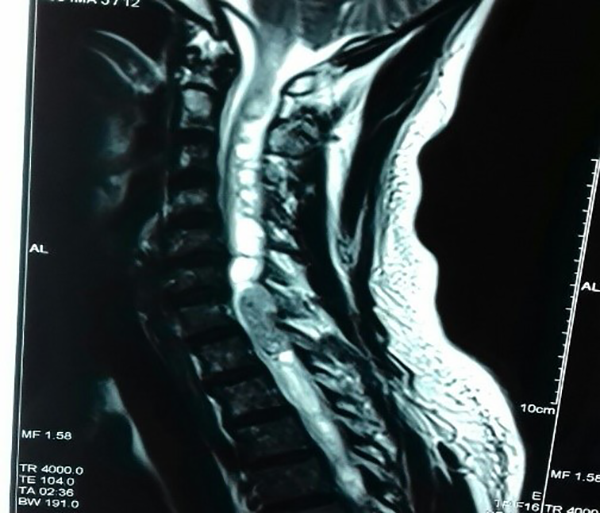

Se trata de un paciente masculino de 44 años de edad, sin antecedentes de importancia para la patología de base, con déficit motor de 2 años de evolución, que inicia a nivel de miembros inferiores y posteriormente afecta también a los superiores hasta provocar dificultad para la marcha. Acude a consulta especializada en silla de ruedas y asistido por familiar con esta historia clínica; se encontró cuadriparesia con paraparesia densa, de predomino derecho, con hiperreflexia generalizada y signo de Babinsky generalizado. Se encontró nivel sensitivo a nivel T5. Se inicia protocolo de estudios de forma inmediata, encontrándose en la RM de médula cérvico-dorsal lesión intraxial a nivel de C7-T1, compatible con probable ependimoma cervical [figura 1]. Se clasifica preoperatoriamente con una Escala de McCormick Modificada, grado 4.

Fig. 1: RM en secuencia ponderada en T2, donde se observa lesión intrarraquídea ocupante de espacio en la porción cervical baja C7- T1, con siringomielia acompañante, supra e infralesional.